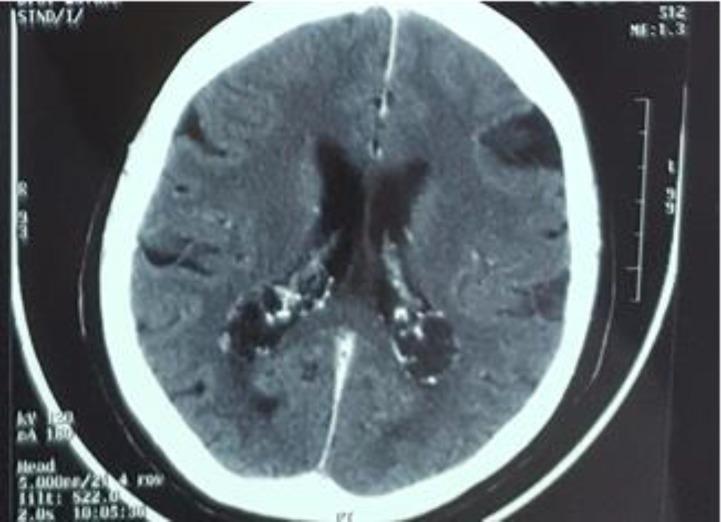

Lung cancer is still diagnosed during the advanced stage of the disease and most patients do not have the opportunity for surgical treatment, despite the new diagnostic equipment that has been made available in recent years, such as the radial and linear endobronchial ultrasound (EBUS) and electromagnetic fiberoptic bronchoscopy. However, novel targeted therapies with second generation tyrosine kinase inhibitors and immunotherapy are available. In this commentary, we will focus on eye metastasis after initiation of tyrosine kinase inhibitors due to epidermal growth factor mutation of lung cancer adenocarcinoma.

尽管近年来出现了新的诊断设备,如径向和线性支气管内超声(EBUS)以及电磁纤维支气管镜,但肺癌仍在疾病晚期才被诊断出来,大多数患者没有机会接受手术治疗。然而,有第二代酪氨酸激酶抑制剂和免疫疗法等新型靶向治疗方法。在这篇评论中,我们将聚焦于因肺腺癌表皮生长因子突变而开始使用酪氨酸激酶抑制剂后出现的眼部转移。